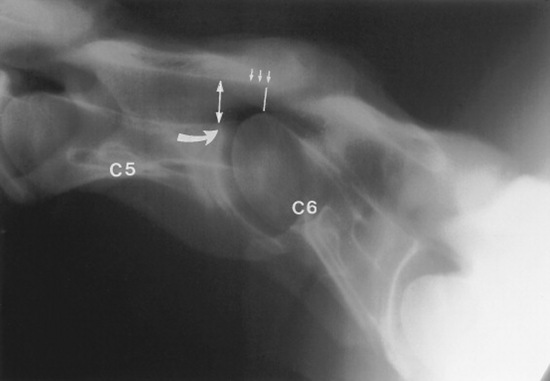

Survey radiographs of the cervical spine are obtained in standing, sedated horses. Cervical radiographs are evaluated by subjective assessment of vertebral malformation and objective determination of vertebral canal diameter.1878 The five categories of cervical malformation subjectively assessed in horses with CVSM are DJD of the articular processes, subluxation between adjacent vertebrae, flare of the caudal physis of the vertebral body, abnormal ossification patterns, and caudal extension of the dorsal laminae1878,1880 (Figs. 35-26 and 35-27). Although the presence of characteristic vertebral malformations supports the diagnosis of CVSM, subjective evaluation of survey radiographs does not reliably discriminate between horses affected and those unaffected by CVSM.1868,1878 DJD of the articular processes of the caudal cervical vertebrae is the most common and severe malformation observed in affected horses.1878 However, degenerative arthropathy occurs in 10% to 50% of nonataxic horses and is the most common and severe vertebral malformation in horses without CVSM.1869,1878 Subjective evaluation of degenerative arthropathy of the articular processes may lead to a false-positive diagnosis of CVSM.1868

Fig. 35-26 Survey radiograph of fifth (C5) and sixth (C6) cervical vertebrae. Bony malformations include flare of the caudal physis (curved arrow, C5), caudal extension of the dorsal lamina (small arrows, C5), and subluxation and malalignment of the C5-C6 articulation. Solid line, Intervertebral canal diameter of C5-C6 articulation; double-headed arrow, intravertebral canal diameter of C5.